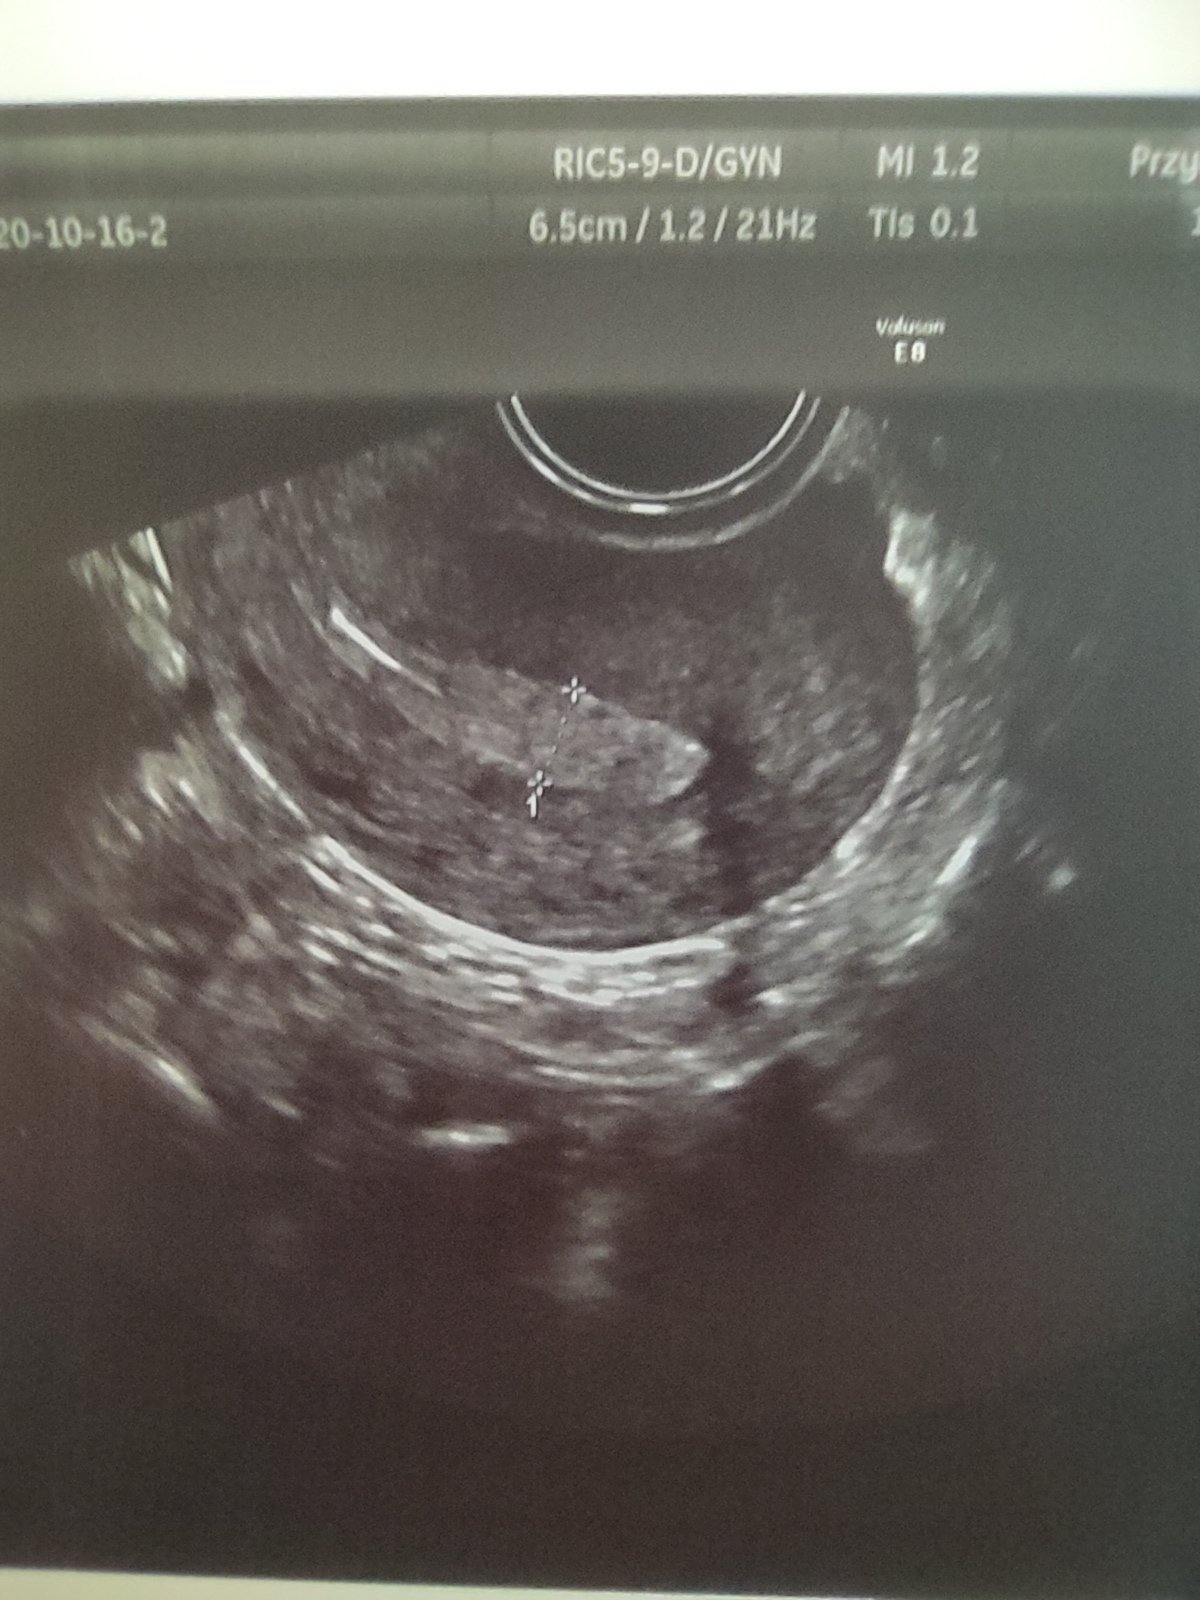

jestem zawsze tak zestresowana że po wejściu do gabinetu wyłącza mi się myślenie. Zapominam zapytać o połowę rzeczy, nie dopytuje tylko przytakuje... I tym sposobem na ostatniej wizycie ginekolog stwierdził że moja macica ma jakieś zwężenie

nie jestem pewna ale coś mówił o jej kształcie. I teraz nie pamiętam czy mówił że to może utrudniać zajście czy donoszenie

boje sie że to macica dwurozna